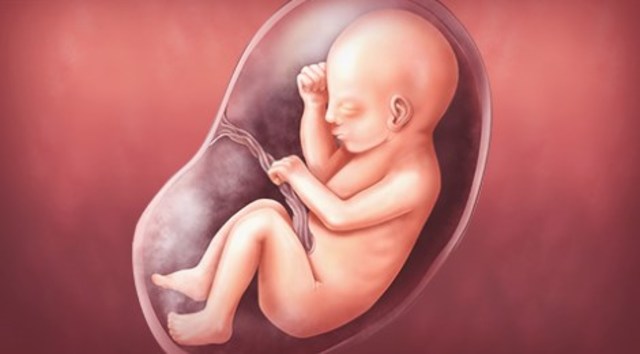

• Week 40 D-Day

Week 40 D-Day

The baby will tuck its legs to its chest and its knees will be touching its nose, mom will start having contractions and her placenta will rupture. It's go time. Once the baby is born and it breathes air for the first time, the heart will send the blood to the lungs in order to be aerated. The baby is born around 20 inches weighing approximately 7.5 pounds

Fact: the babies' skull is soft in order for it to have easy passage through the vagina at birth